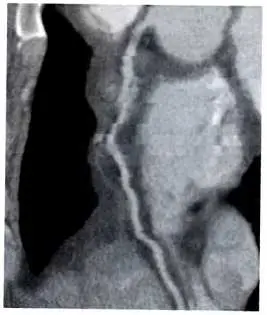

圖中顯示的是冠狀動脈(根據解剖位置與垂直走向,推測為右冠狀動脈,Right Coronary Artery, RCA)的電腦斷層曲面重建(Curved Planar Reformation, CPR)影像。在血管走向上可以明顯觀察到血管輪廓出現不連續、錯位與模糊的現象,這呈現了典型的階梯狀假影(Stair-step artifact)或移動假影(Motion artifact)。這類假影主要是由於心臟在掃描過程中的快速搏動,導致在不同心跳週期或不同切面掃描時血管處於不同的空間位置,使得後處理重建時無法完美接合所造成。